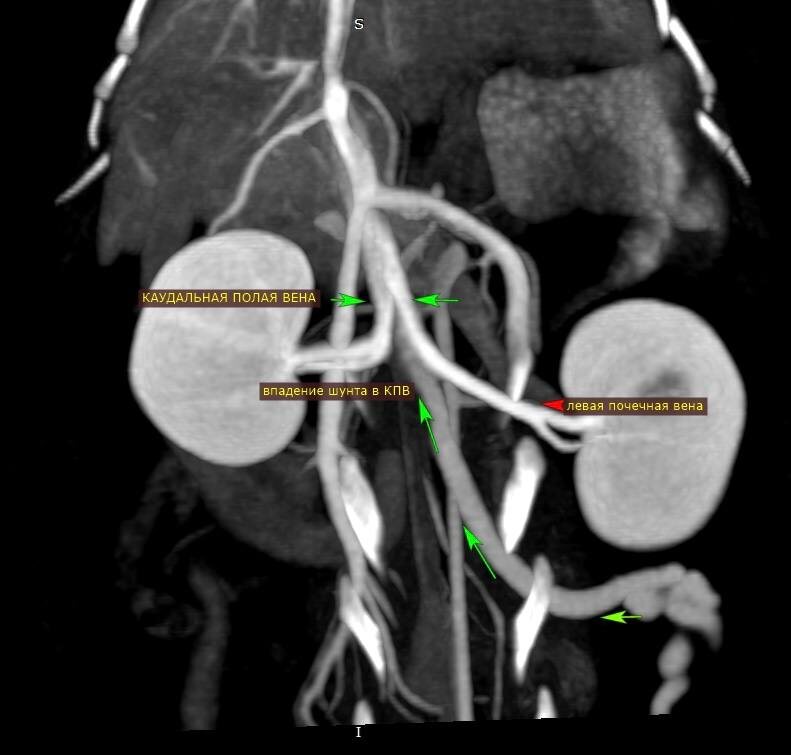

Но, благодаря проведенной КТ диагностике у Аси подтвержден ПСШ (порто-системный шунт). Да, эта аномалия встречается не только у собак.

✅ПСШ - это врожденная сосудистая аномалия, из-за которой значительная часть венозной крови от кишечника попадает в системный кровоток, минуя печень, т.е. не подвергаясь "очистке". Такая кровь содержит токсичные, в первую очередь, для головного мозга вещества.